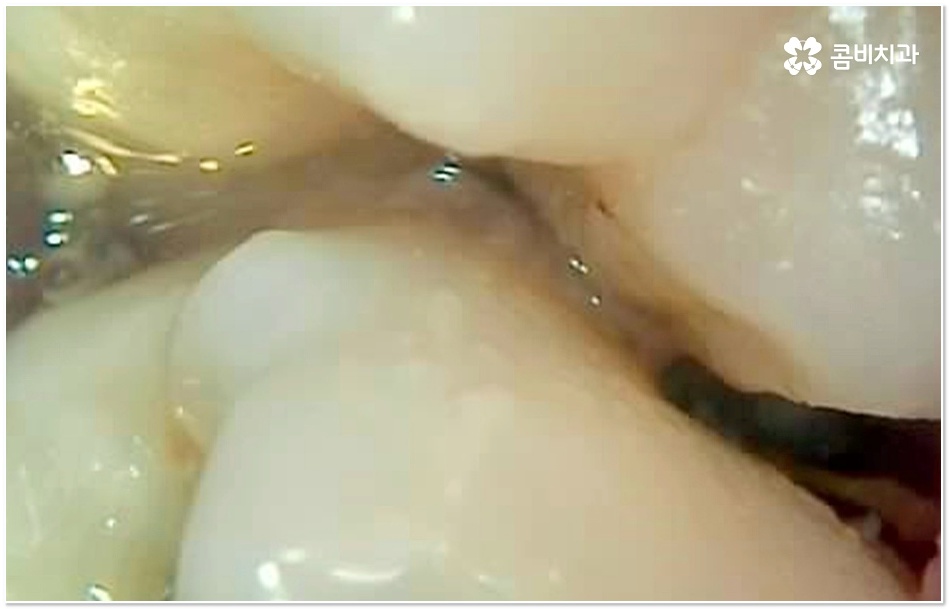

특히 그 중에서도 사랑니와 어금니 사이에 생긴 치아 사이 충치 는 구강 내 가장 안 쪽에 있기 때문에 제 때 발견하기도 어렵고 위치상 치료하기가 쉽지 않아서 병증의 진행 여부 및 상황에 따라 사랑니 뿐만 아니라 어금니까지 발치를 해야 하는 안타까운 상황에 이를 수도 있으니 그 전에 알맞은 대처를 해 주시는 것이 필요할 거예요.

사랑니 같은 경우는 영구치 중에서 가장 마지막에 자라기 때문에 다른 치아와 턱 뼈에 밀려 비좁은 공간에 누운 채 자리를 잡거나 부분적으로만 나오는 등 비정상적으로 맹출될 가능성이 높은 치아인데, 그렇지 않아도 위치상 관리가 잘 되지 않는 곳에서 앞 어금니와의 사이에 작은 틈새가 생기게 되면 음식물이 더욱 잘 끼고 빠지지 않으므로 치아 사이 충치 가 쉽게 발생하게 되는 거예요.

사랑니와 어금니 인접면에 치아 사이 충치 가 발생할 경우 육안으로도 보기 힘들 뿐 아니라 엑스레이를 찍었을 때에도 쉽게 발견하기 힘들 수 있기 때문에 초기에 알아차리지 못하고 치료 시기를 놓치는 경우가 종종 생기며 손상 정도가 많이 심각하거나 위치상 사랑니 발치 후에도 뿌리 끝 염증이 매우 심하거나 치아 사이 충치 로 손상이 심해 치료가 불가능한 케이스의 경우 불가피하게 어금니까지 발치를 해야 할 수 있으므로 이와 같은 상황에 이르지 않도록 평상시에 정기 검진을 꼬박꼬박 받아주는 것이 조기 대처 및 예방 등에 있어 여러 모로 유리하다고 할 수 있습니다.